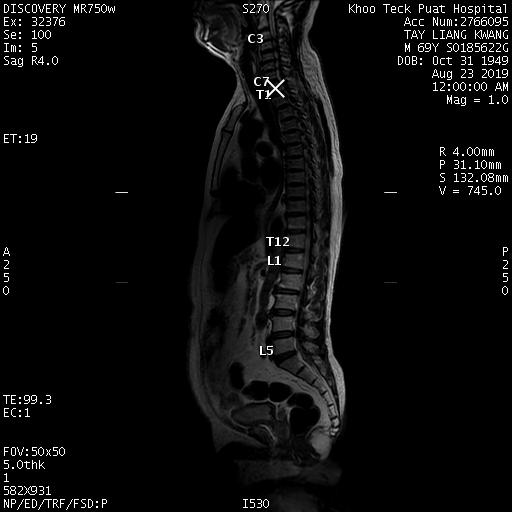

| Patient: TAY LIANG KWANG (M) | Birth date: 10/31/1949 | ID: S0185622G |

| Study | ID | Date | Accession # | Thumbnails | Report | XR ELBOW, AP & LAT, LEFT | 2766356 | 08/21/2019 | 2766356 | ... | MR WHOLE SPINE (FULL STUDY) | 32376 | 08/23/2019 | 2766095 | ... | XR CERVICAL SPINE, AP & LATERAL | 2765876 | 08/20/2019 | 2765876 |